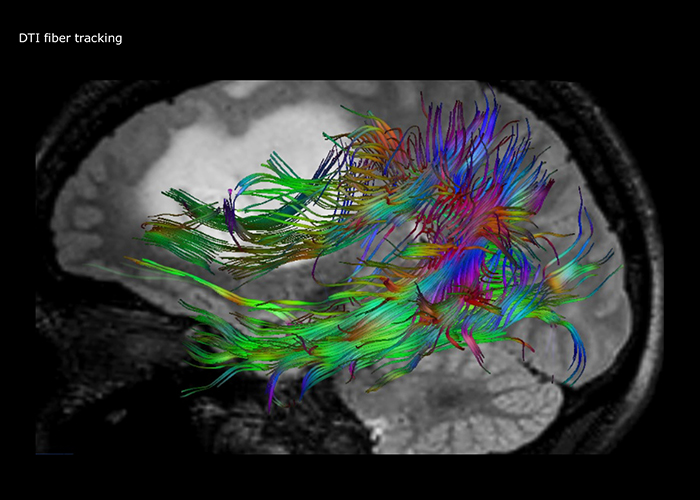

“The biggest challenges are properly characterizing the lesion and giving the surgeon all the information needed, such as the location of vessels and functional areas. Sometimes a very comprehensive exam is necessary, such as when a mass has been discovered at another hospital after which the patient is referred to us. We then do both lesion characterization and preoperative imaging in one exam, so both morphologic and functional assessment. For morphologic assessment we will use pre- and post-contrast T1-weighted imaging, FLAIR to assess infiltration, and diffusion. For functional characterization we will perform perfusion, spectroscopy, and susceptibility weighted imaging to look for micro vessels or micro hemorrhage inside the lesion[4]. For preoperative imaging we perform specific morphologic imaging that is compatible with the navigation system; depending on the location of the tumor, we would do fMRI or DTI.”